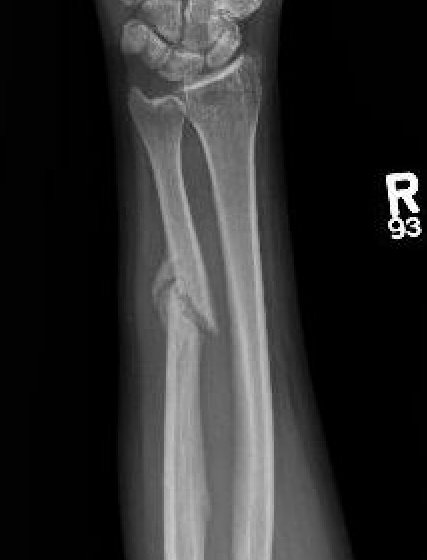

Operative management

Indications

Acute fractures

- > 50% displacement

- > 10 degrees angulation

- midshaft ulna fractures - higher risk of nonunion

Nonunions